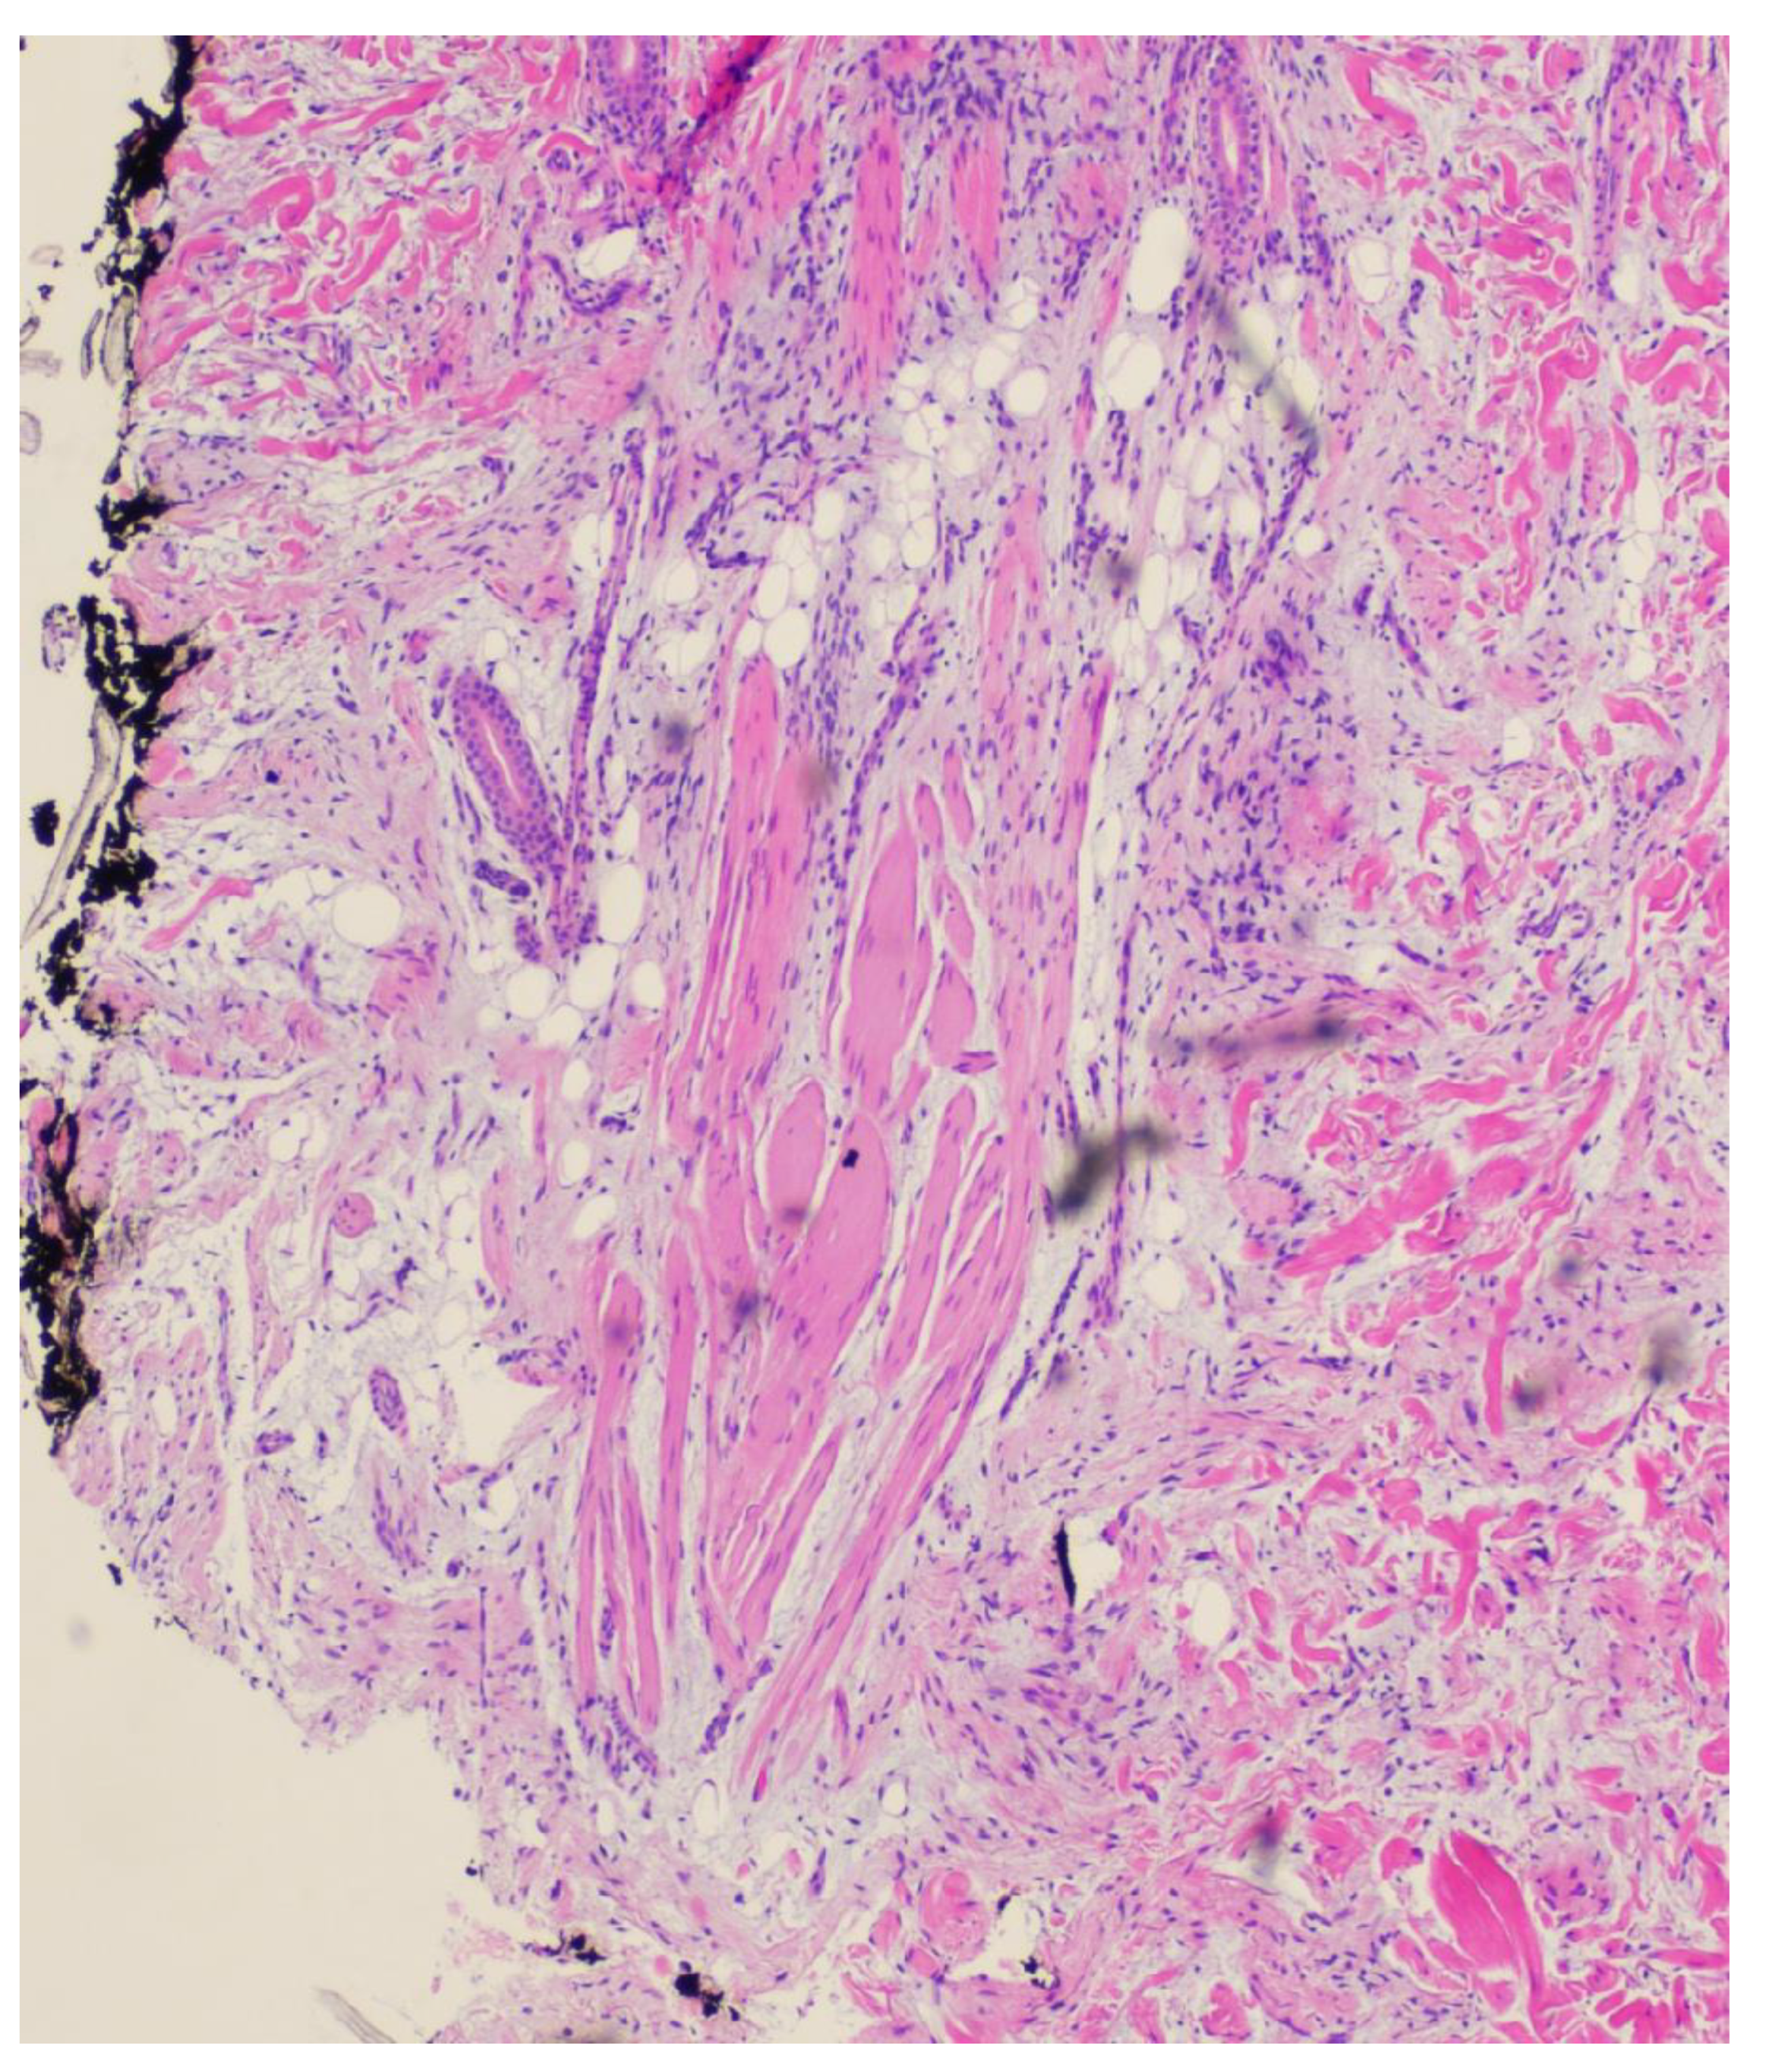

Figure 1). A punch biopsy was obtained and revealed atypical myxoid spindle cell neoplasm and involved margins with overlying mildly atypical compound melanocytic nevus. The specimen also displayed CD34 positivity (histopathology displayed in

Figure 2,

Figure 3,

Figure 4,

Figure 5,

Figure 6,

Figure 7,

Figure 8 and

Figure 9). A diagnosis of spindle cell lipoma was reached, and wide local excision with 2 cm margins was performed and subsequent pathology revealed clear margins.

Histopathologically, the presence of an atypical myxoid spindle cell neoplasm with CD34 positivity further complicated the diagnosis. The biopsy also revealed an overlying mildly atypical compound melanocytic nevus, which is an unusual finding in SCL and raised concerns about a potential collision tumor or a misdiagnosis.